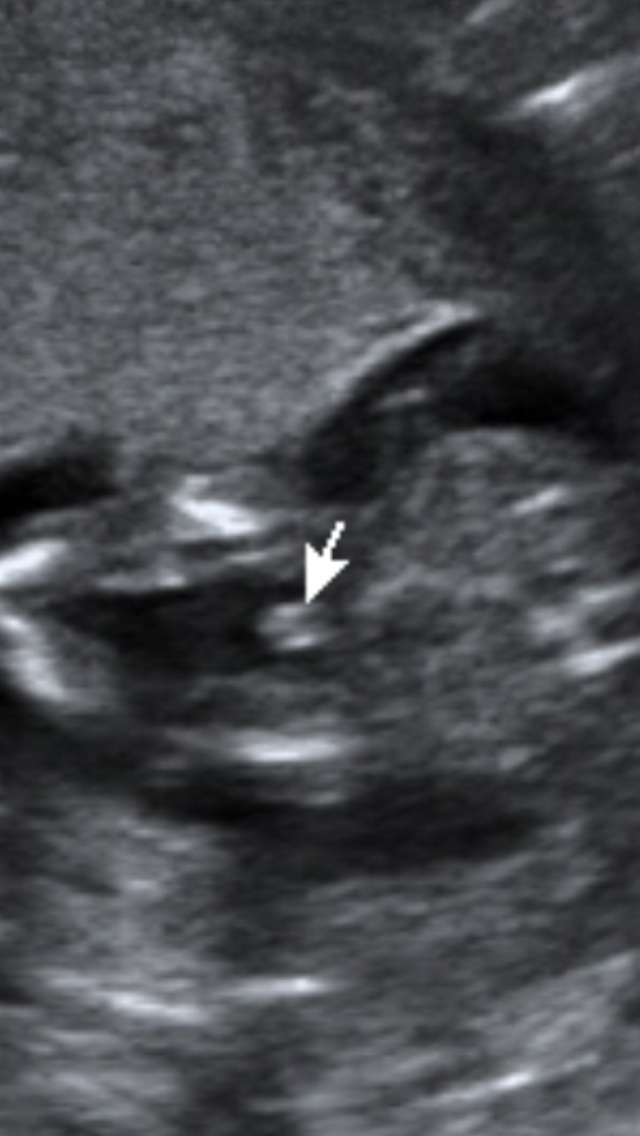

Hi everyone. We had our gender scan 2 weeks ago when I was 16 weeks. The tech predicted boy but I'm not so sure. We have 3 beautiful boys already and their scan pictures looked totally different. The tech also said that he/she was in an awkward position - lying too close to the placenta. I've been searching the internet and found this website very helpful. Would anybody care to take a guess for me? Attachment 18298